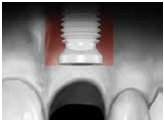

於100/06/07重新放置兩顆植體

並於100/10/25將中間兩顆植體做二階接出

由於前後植體的高低差距太大,決定將中間兩顆高度較為一致的植體假牙做連結,但前後兩顆做單顆假牙的設計。

100/11/21 補綴完成

目前植體周圍的組織都很理想健康並追蹤中。